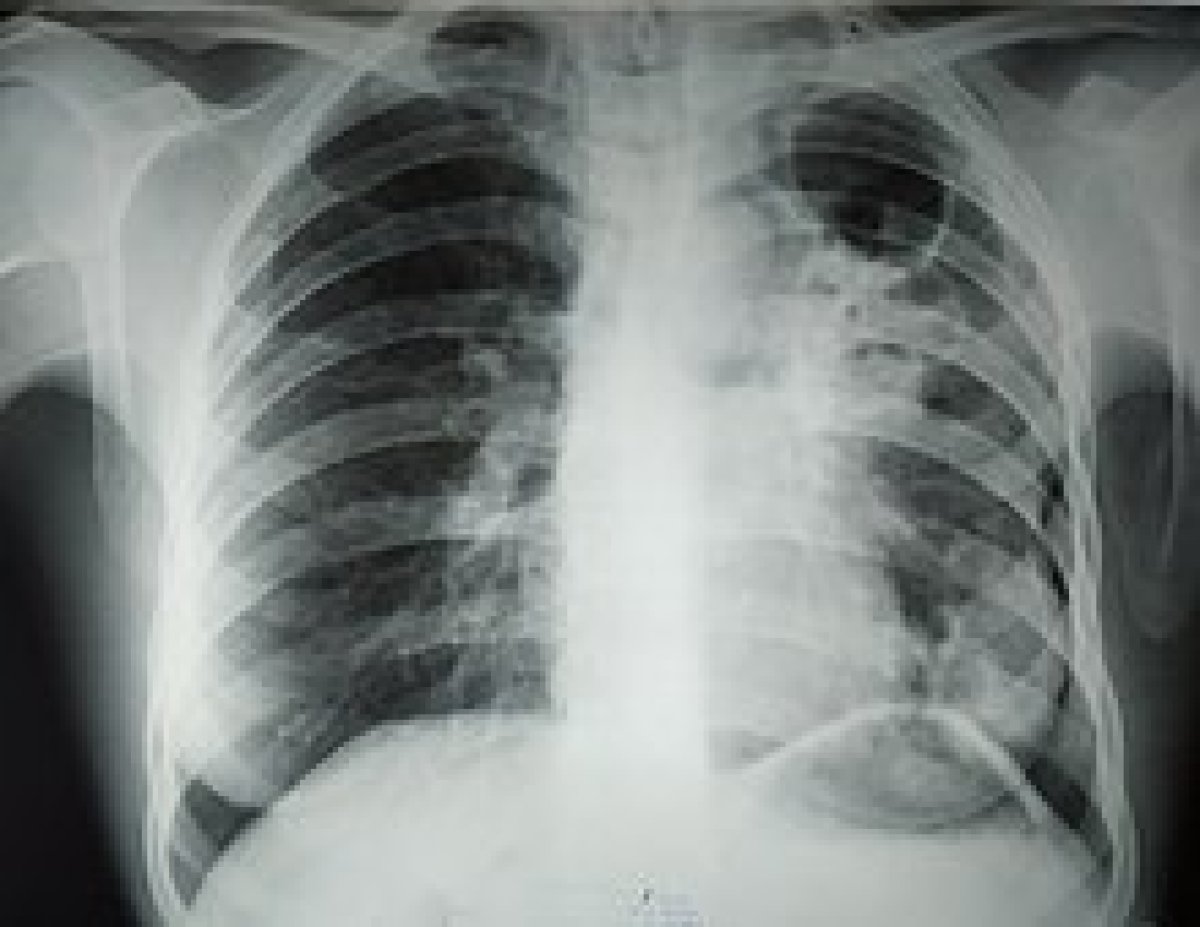

210 случаев туберкулёза зарегистрировано в Северо-Казахстанской области в 2022 году. Рост заболеваемости на 23% зафиксирован в Петропавловске, передает Astana TV

В 2 раза чаще стали болеть подростки 15-17 лет, сообщили в Комитете санитарно-эпидемиологического контроля. "Рост заболеваемости туберкулезом наблюдается в г. Петропавловске на 22,25%, на 10 случаев в Кызылжарском районе, на 7 случаев в Айыртауском районе, на 4 случая в Есильском районе и Уалихановском районе", - отметили в ведомстве. Также там назвали основные признаки заболевания. Это - кашель более 2 недель, боли в грудной клетке, ночная потливость, снижение массы тела, длительное повышение температуры до 37-37,5 градусов, общая утомляемость.